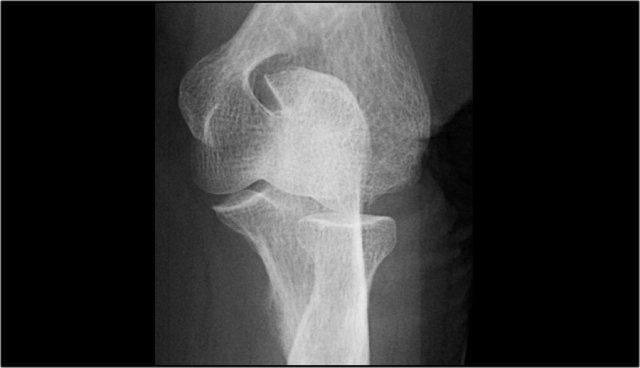

Arthrosis in valgus overload syndrome

Due to the valgus overload there are shear forces on the posteromedial part of the humeroulnar joint.

Notice the subchondral sclerosis seen on the T1W-image (red arrow).

On the T2W-image there is subchondral bone marrow edema and cartilage loss (yellow arrow).

These are images of a 20 year old baseball pitcher.

Scroll through the images.

On the coronal images there is a beautiful anterior bundle of the UCL, but notice that there is osteophyte formation on the medial part of the joint (red arrow).

As we go further posteriorly there is a small area of low signal intensity (yellow arrow), which is an avulsion of part of the UCL.

This is better appreciated on the radiograph.

Continue with the axial scan.

As we look on the axial scan, we can appreciate the huge osteophyte formation.

Notice that the ulnar nerve (blue arrow) is next to these osteophytes and these patients may present with ulnar neuropathy.